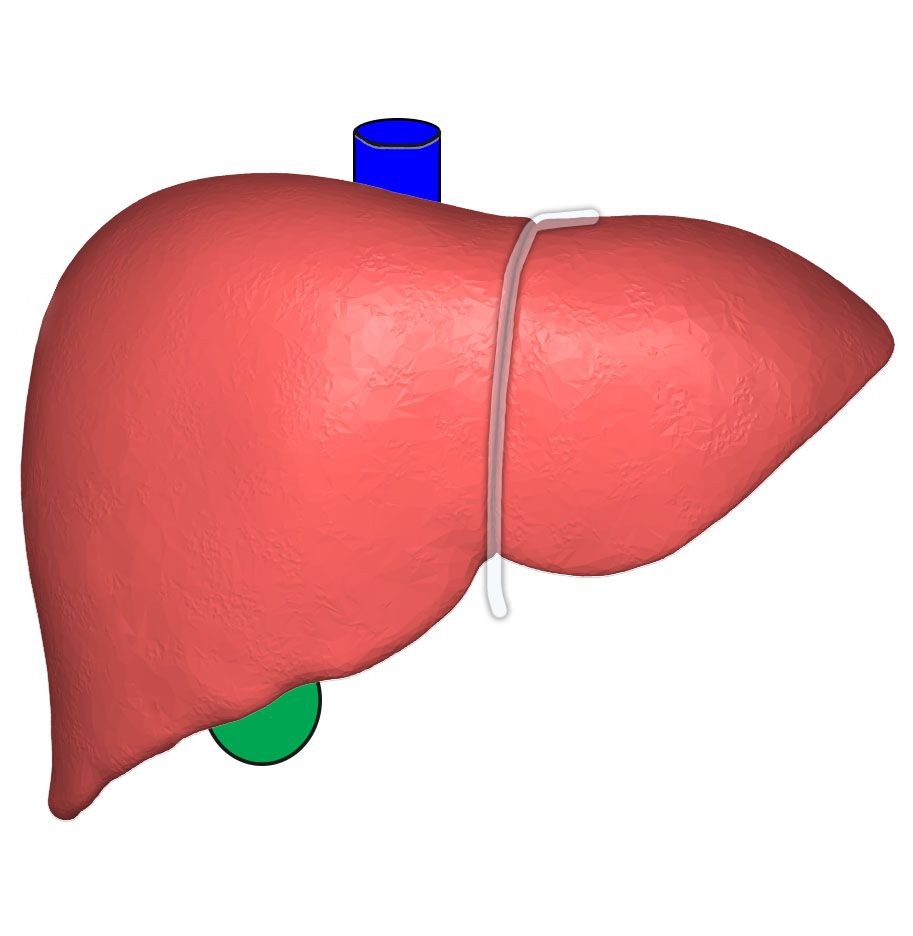

Печень, один из самых крупных и важных органов человеческого тела, выполняет множество жизненно необходимых функций, включая фильтрацию токсинов и производство жизненно важных белков. В данной статье мы рассмотрим, как наглядные изображения печени могут помочь лучше понять её структуру, функции и возможные заболевания. Использование рисунков и диаграмм делает сложные биологические процессы более доступными для понимания, особенно важно это для студентов, врачей и пациентов, стремящихся глубже изучить этот ключевой орган.

Печень рисунок